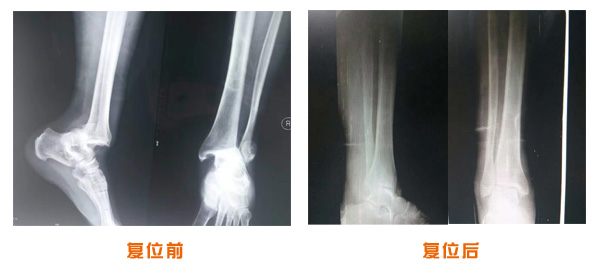

肥城市安駕莊梁氏骨科醫(yī)院是一所以梁氏手法正骨配合膏藥為特色的現代化專科醫(yī)院。

梁氏骨科術始創(chuàng)于清雍正年間,歷經八代,至今已有三百年歷史。據1929年泰安縣志載“梁瑞圖先生,字增生,號蓮峰,安駕莊人,精岐黃并發(fā)明接骨,凡跌打車凡跌打車軋皮不破而碎骨者......【詳細】 |